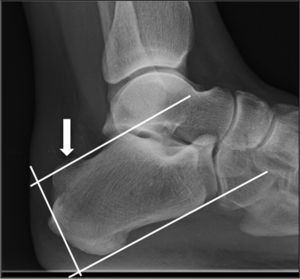

El diagnóstico se realiza por la clínica y por las imágenes radiológicas con el método de medición de las líneas de inclinación paralelas (parallel pitch lines [PPL]), en una radiografía lateral del tobillo. Este método consiste en trazar una línea tangente a la superficie inferior del calcáneo, y otra paralela a esta en la cara superior, a la altura del punto más alto de la cara posterior de la superficie de la articulación subastragalina. Si la tuberosidad supera esta línea se considera deformidad de Haglund (fig. 1)2,5. En algunos casos el diagnóstico se puede completar con ecografía o RMN2,6.